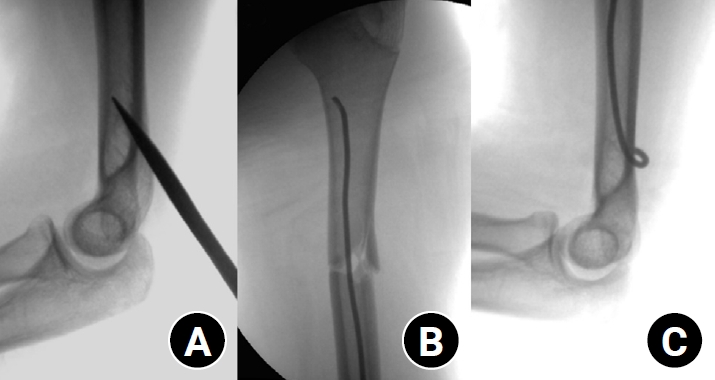

A posterior entry technique through the distal humeral cortex was used in all cases. A small longitudinal incision was made over the posterior aspect of the distal humerus just proximal to the olecranon fossa. The triceps muscle was bluntly split to expose the posterior cortex, and an awl was used under fluoroscopic guidance to create the entry portal into the medullary canal (Fig. 1).

Fig. 1.

Intraoperative fluoroscopic images demonstrating the surgical technique of elastic stable intramedullary nailing for a pediatric humeral shaft fracture. (A) The entry point was created at the posterior cortex of the distal humerus using an awl under fluoroscopic guidance. (B) The pre-bent elastic nail was advanced across the fracture site under continuous fluoroscopic visualization. (C) The distal ends of the nails were contoured and buried subcutaneously to minimize soft-tissue irritation.

Fig. 1. Intraoperative fluoroscopic images demonstrating the surgical technique of elastic stable intramedullary nailing for a pediatric humeral shaft fracture. (A) The entry point was created at the posterior cortex of the distal humerus using an awl under fluoroscopic guidance. (B) The pre-bent elastic nail was advanced across the fracture site under continuous fluoroscopic visualization. (C) The distal ends of the nails were contoured and buried subcutaneously to minimize soft-tissue irritation.